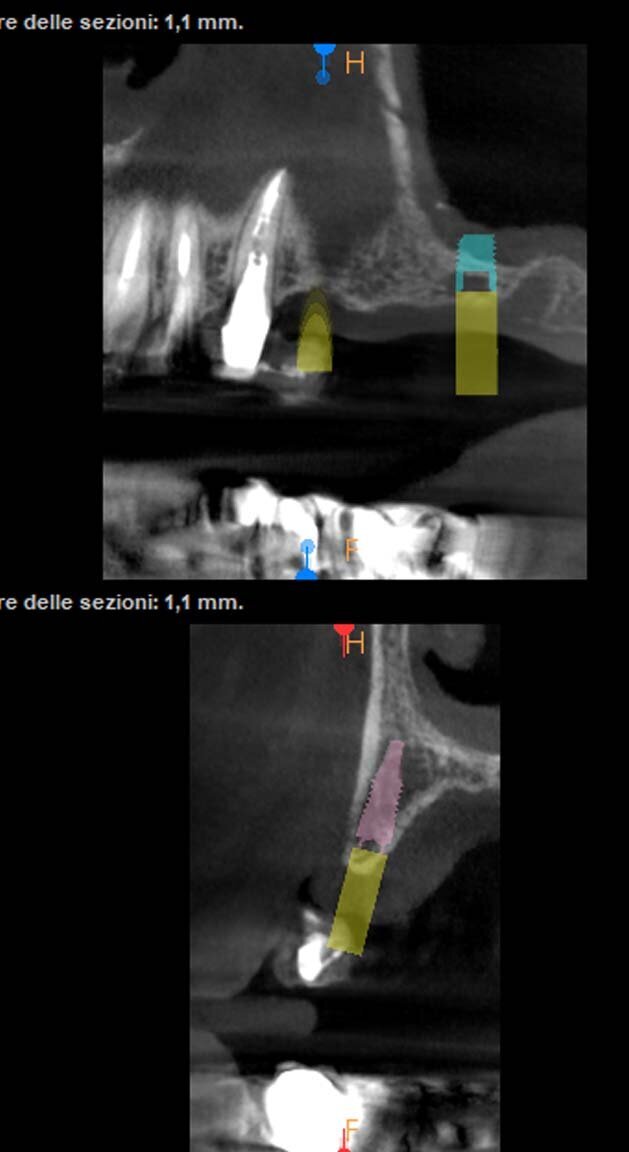

Il paziente di 50 anni in buono stato di salute, necessitava di una riabilitazione di tutta l’arcata superiore sia con impianti nei settori posteriori sia con corone sui denti frontali. Mentre nel sestante superiore destro era presente una quantità d’osso ideale per l’inserimento di impianti di diametro e lunghezza considerati standard, nel sestante sinistro era presente una quantità d’osso insufficiente sia verticalmente che orizzontalmente (Figg. 1-4). A causa dei timori del paziente sono stati esclusi interventi invasivi per incrementare i volumi ossei e si è deciso di inserire in posizione 24 un impianto BTI 3.0 3,3 x 10 mm e in posizione 26 un impianto BTI standard 3,7 x 5,5 mm con un minirialzo contestuale del seno mascellare.

È stato eseguito un lembo a spessore totale senza tagli verticali di rilascio e una regolarizzazione della cresta ossea per mezzo di un raschietto per osso, che ha permesso di ottenere una quantità ulteriore di osso oltre a quello ottenuto per mezzo della fresatura a basso numero di giri secondo la procedura BTI. L’osso ottenuto è stato mischiato con gel piastrinico ottenuto mediante centrifugazione del sangue del paziente secondo la metodica PRGF Endoret ed inserito in parte all’interno dell’osteotomia del dente 26 a protezione della membrana sinusale e in parte protezione della parete ossea vestibolare del dente 24 che era particolarmente sottile. Dopo aver applicato i tappi di guarigione i lembi sono stati suturati per ottenere una guarigione sommersa (Figg. 5-7). Dopo quattro mesi di guarigione gli impianti furono scoperti e due pilastri Multi-im sono stati avvitati con i relativi tappi di guarigione.